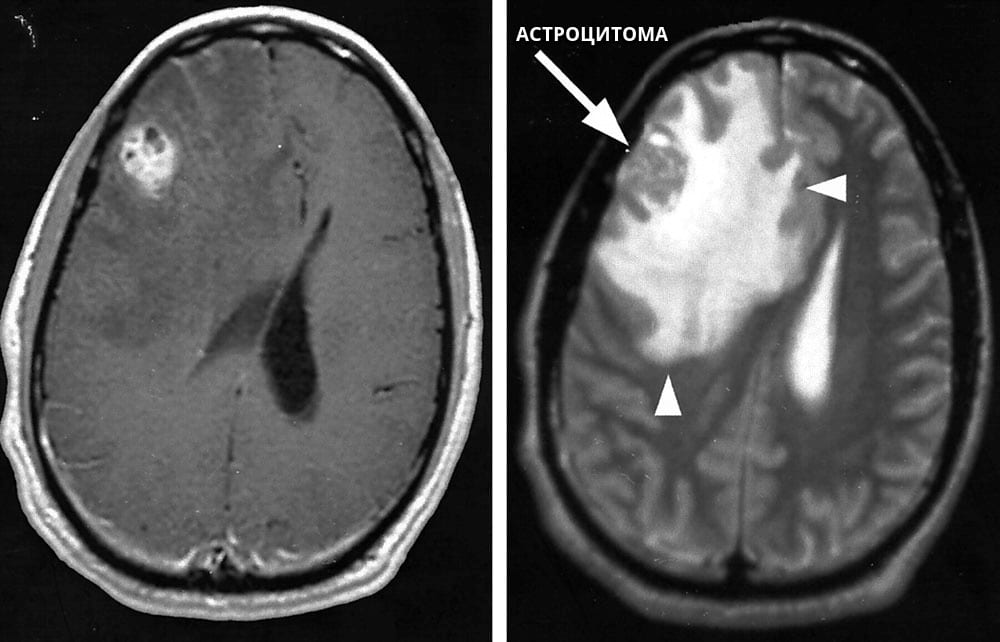

Астроцитома головного мозку – одна з найбільш небезпечних пухлин, адже на неї припадає більша частина